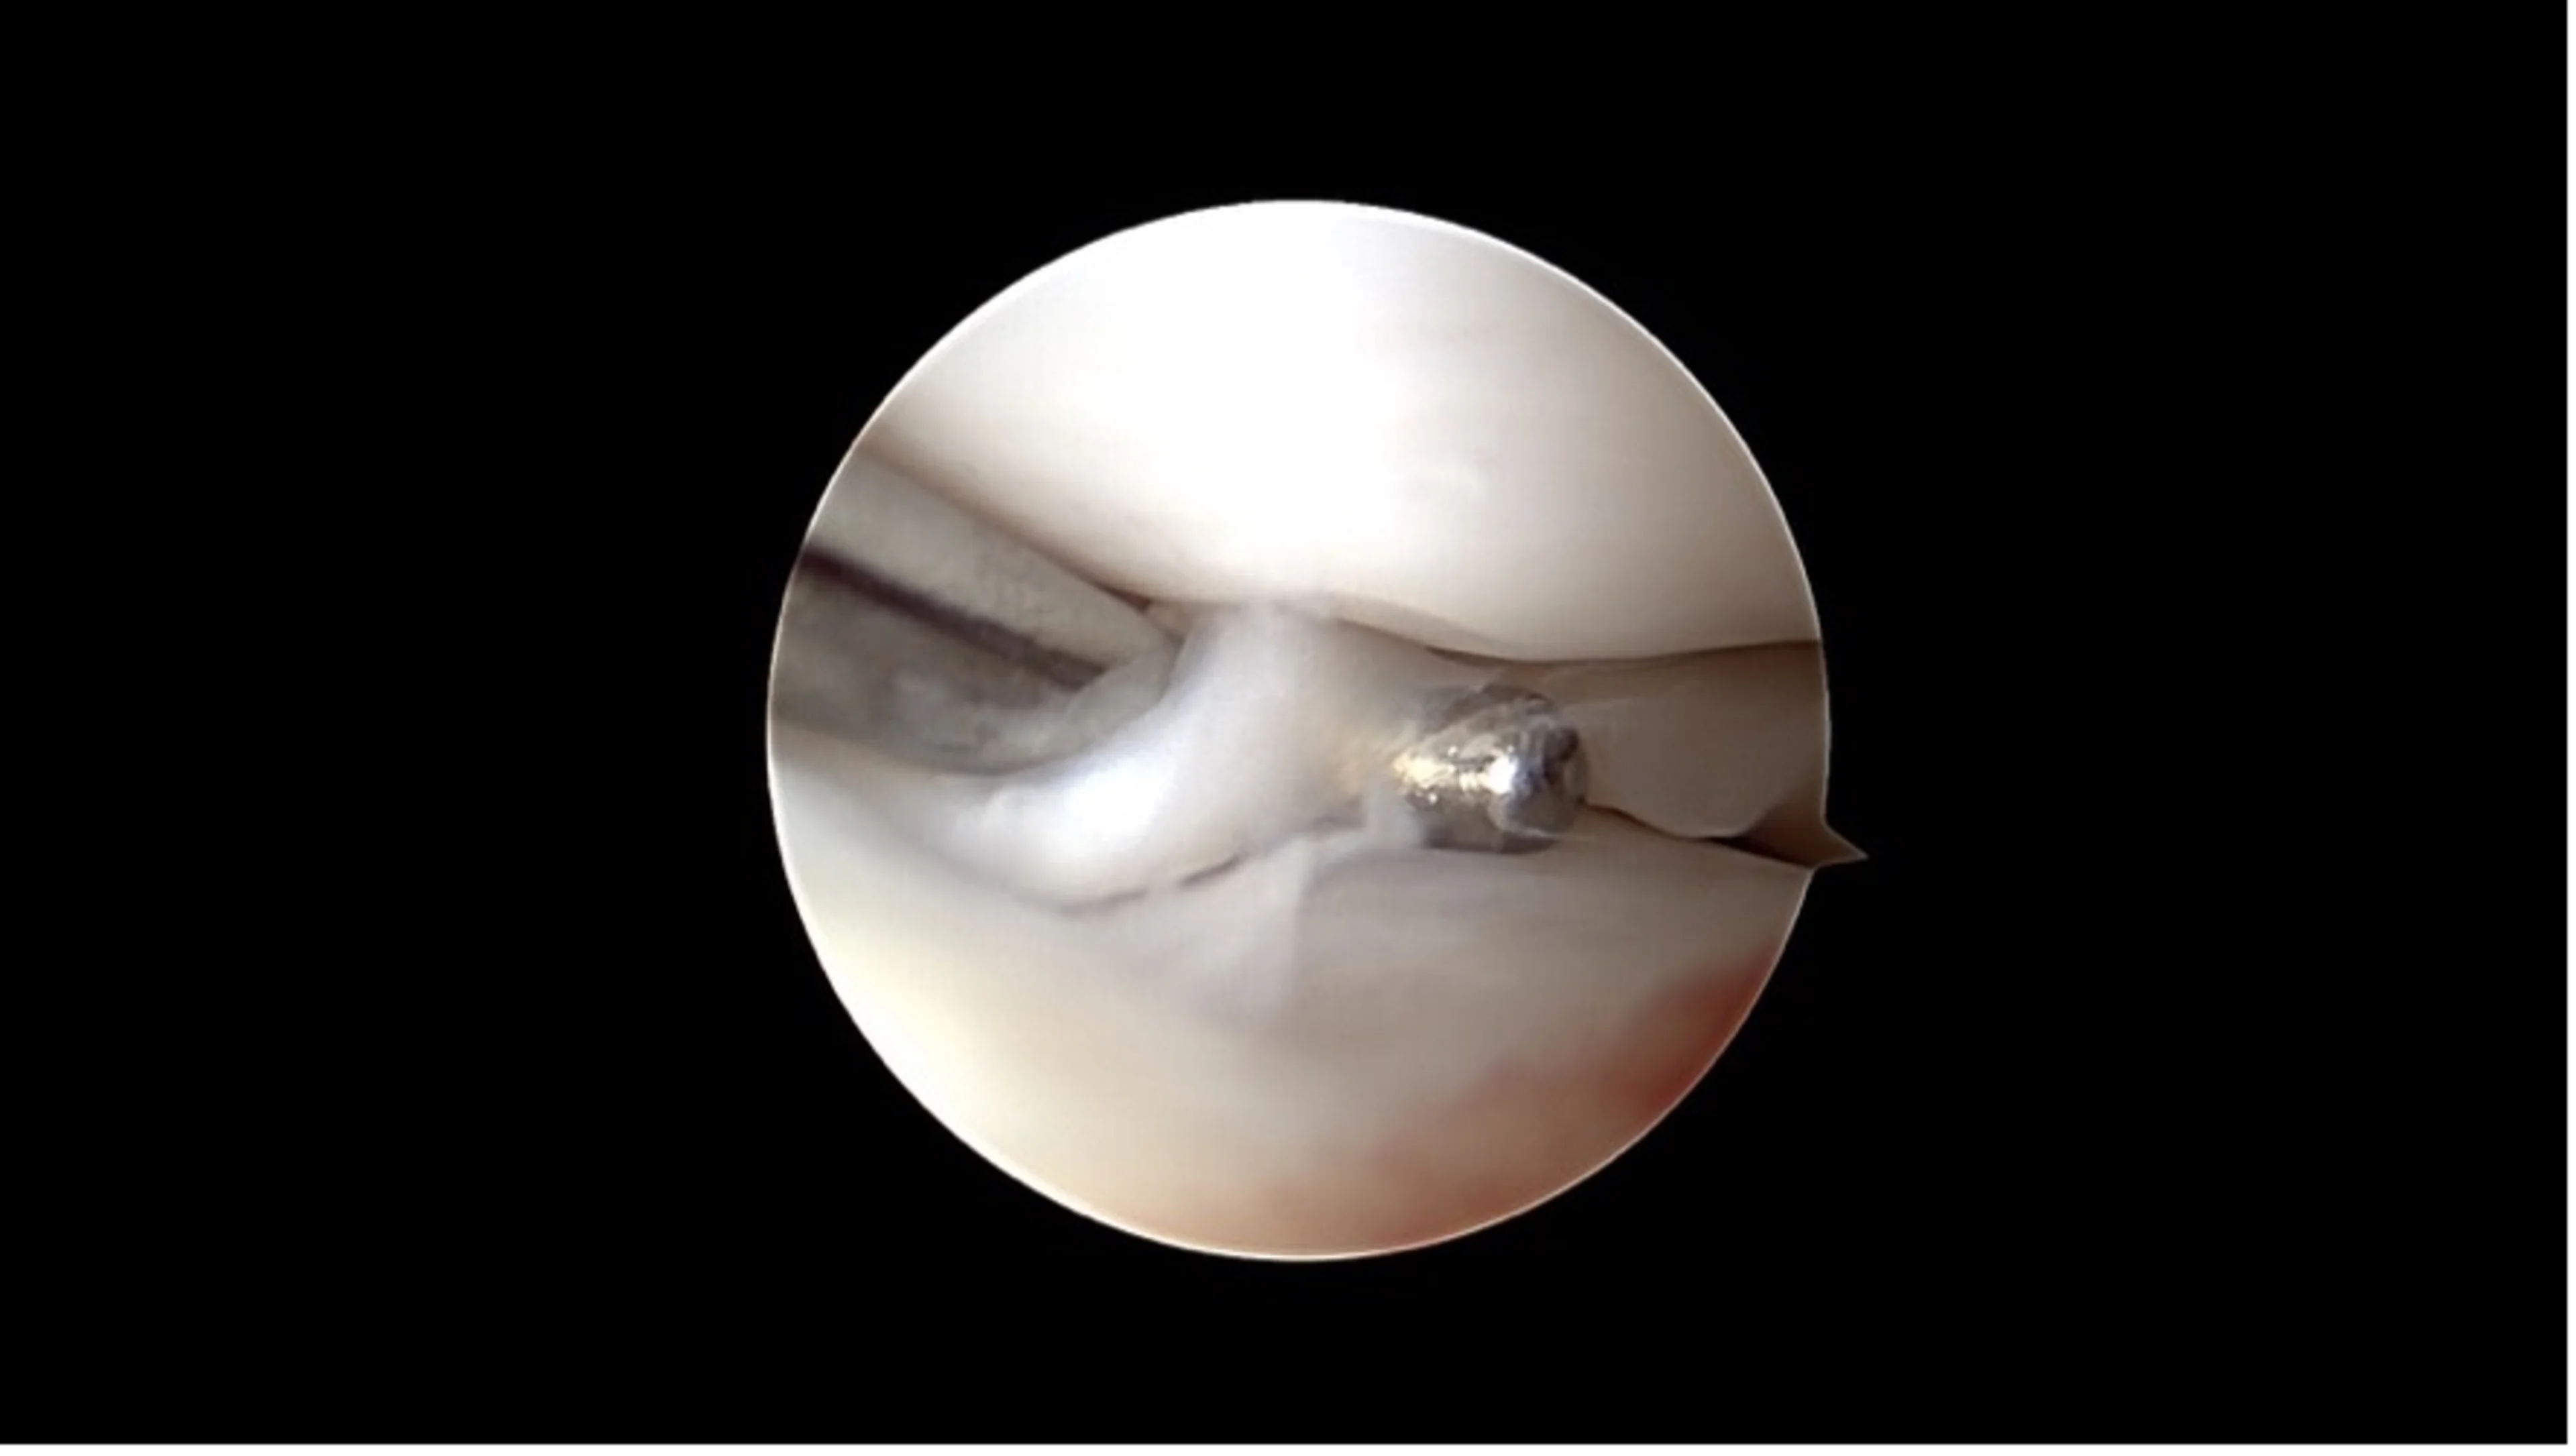

Ein beginnender Kreuzbandriss versteckt sich unter dem auf dem ersten Blick unauffälligen restlichen Kreuzband

Ein kompletter Kreuzbandriss

Arthroskopie: Diese Technik ermöglicht eine direkte Sicht auf das Gelenkinnere mit Hilfe einer kleinen Kamera. Über nur wenige Millimeter grosse Hautöffnungen lassen sich Veränderungen am Kreuzband sowie begleitende Schäden wie Meniskusrisse erkennen und in vielen Fällen auch direkt behandeln.

Korbhenkel-artiger Meniskus Riss

Nanoskopie: Noch feiner als die Arthroskopie bietet die Nanoskopie die Möglichkeit, mit besonders kleinen Instrumenten und hochauflösender Bildtechnik im Gelenk zu arbeiten. Das Verfahren ist besonders geeignet für kleinere Hunde. Beide Methoden sind minimalinvasiv, verursachen wenig Gewebetrauma und ermöglichen eine schnellere Erholung.